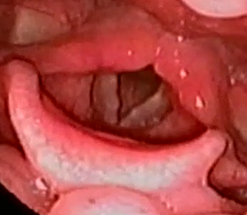

喉頭肉芽腫症

声帯の後方にある突起部に生じる両性の腫瘤です。症状は、喉の違和感で、咳払いが癖になっている人もいます。

声帯の後方にある突起部に生じる両性の腫瘤です。症状は、喉の違和感で、咳払いが癖になっている人もいます。

治療は、投薬や切除です。